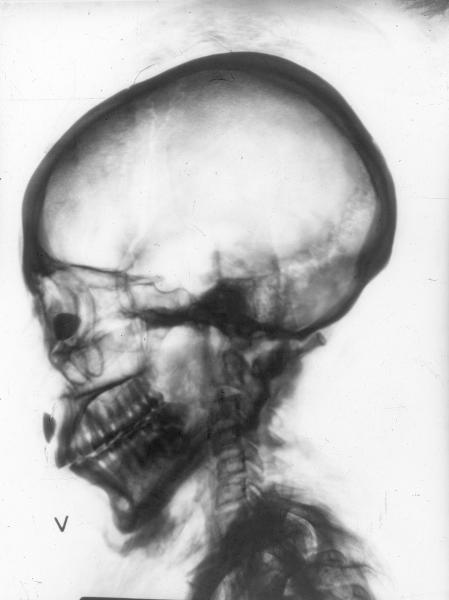

• Röntgenbild av mumie, Bakenren

• Fotograferad 1960 av St Eriks Sjukhus.